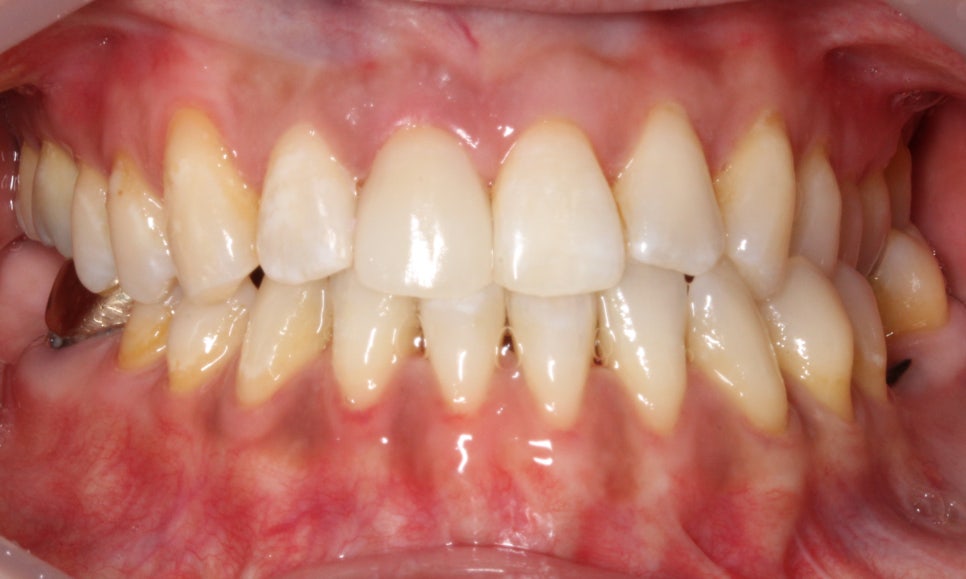

□ 앞니 노화

출처:투디 치과/앞니 노화 사례의 블링스 전후 사진입니다.

앞니 노화의 전, 후 사례입니다.

앞니가 노화되고 치아도 마모된 전 사진은

블링스를 만나고 자연스럽게 개선된 모습입니다!